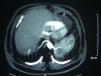

Presentamos el caso de un varón de 64años, exfumador, con criterios clínicos de bronquitis crónica, con oxígeno domiciliario desde hace más de 10años y SAHS en tratamiento con CPAP nocturna. Ingresó en 1990 por neumonía en el lóbulo inferior izquierdo (LII) secundaria a cuadro de cuasi ahogamiento en agua de mar. Durante el seguimiento persistía una condensación triangular en el LII con TAC y fibrobroncoscopia no diagnósticas. Se realizó punción transtorácica guiada por TAC con citología negativa para malignidad y estudio microbiológico negativo. Presentó varios ingresos en los últimos años por agudización de la EPOC. Se solicitó nueva TAC torácica en 2004 por condensación en LII, siendo diagnosticado de posible secuestro pulmonar (SP) intralobar izquierdo. El paciente rechazó realizar nuevos estudios. En 2009 ingresó por neumonía, presentando en la TAC torácica (fig. 1) una formación compleja de unos 6-7cm, en situación medial de LII, nutrida de un voluminoso vaso originado en la aorta torácica inferior y con drenaje a venas pulmonares, correspondiendo a un SP intralobar con probable sobreinfección; en situación simétrica, contralateral, existía otro vaso anómalo con origen también en la aorta, correspondiente a otro SP intralobar en dicha región derecha. Tras mejoría con tratamiento es dado de alta para seguimiento en consulta, pero no acude a las revisiones. La mayoría de los SP intralobares son unilaterales, siendo muy raros los bilaterales1. Para Kohler el SP fue descrito por primera vez por Rokitanski y Rektorzik en 1861 y no fue hasta 1946 cuando lo da a conocer Pryce2 como entidad clínica. En 1972 Felson et al.3 comunicaron un caso de SP bilateral confirmado por anatomía patológica. En 1977 Karp et al.1 describen otro caso en una niña de 13años que presentó una masa en LII descubierta tras una radiografía de tórax. Se le realizó TAC y arteriografía pulmonar, evidenciándose un SP intralobar izquierdo, ya sospechado, y un SP derecho no observado anteriormente. Existen algunos casos publicados desde entonces coincidiendo en edad pediátrica o adolescentes. Es en 2009 cuando Yamamura et al.4 explican el procedimiento quirúrgico que se realizó a un paciente de 44años que presentaba un SP bilateral intra y extralobar. Wei y Li5 analizaron 2.625 casos de SP en 2011, entre los cuales tan solo 3 eran bilaterales y 2 de ellos intralobares. El caso que presentamos cumple la doble excepcionalidad de tratarse de un paciente con un SP bilateral intralobar y ser de edad avanzada. Ha presentado neumonías de repetición de aspecto cambiante en LII, en el que las pruebas diagnósticas no llegaron a ser concluyentes. En la TAC previa al ingreso actual ya se describía la posibilidad de SP. La existencia de condensaciones de repetición, especialmente si se producen en LII, obliga a contemplar el diagnóstico diferencial de diversas patologías como el SP, neumonías de larga evolución, enfermedad obstructiva crónica o tumores pulmonares6. Tradicionalmente el diagnóstico de SP requería de realización de angiografia pulmonar para poner de manifiesto vascularización anómala. La existencia de nuevas técnicas como la angioTAC de última generación permite reconstrucciones vasculares de alta resolución que pueden obviar la arteriografía, así como poner de manifiesto malformaciones congénitas evitando técnicas más invasivas. En cuanto al tratamiento, propondríamos la actuación sobre el SP izquierdo, por ser el sintomático, mediante cirugía o VATS, siendo esta última técnica menos invasiva.